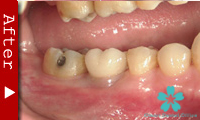

歯を一本だけ失った場合

“失われた1本の歯根の代理品”としてインプラントを1本だけ使って失った歯の部分を修復する方法は、最も洗練された治療方法であり、審美的にも満足のいく結果が得られます。

1本のインプラントによってあたかも自分の天然歯のように自然に感じられます。顎骨の”萎縮”の心配もなく、本来の骨量を維持できます。

ブリッジを入れる時のように、健康な隣の歯を削る必要がありません。